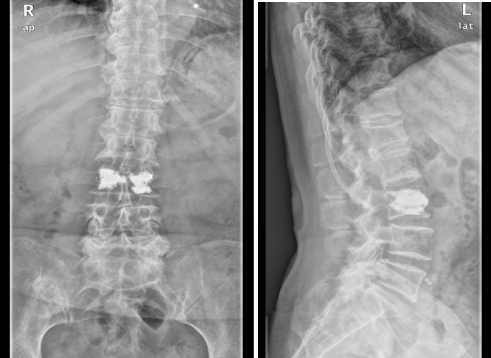

术后